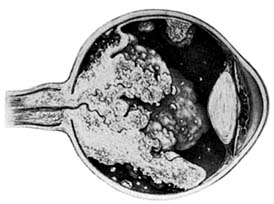

Retinoblastomas may exhibit outward (exophytic) or inward (endophytic) growth-either or both. The latter then extend into the vitreous (Figure 10-33). Both types gradually fill the eye and extend through the optic nerve to the brain and, less commonly, along the emissary vessels and nerves in the sclera to the orbital tissues. Occasionally, they grow diffusely in the retina, discharging malignant cells into the vitreous or anterior chamber, thereby producing a pseudoinflammatory process and mimicking retinitis, vitritis, uveitis, or endophthalmitis. Microscopically, most retinoblastomas are composed of small, closely packed, round or polygonal cells with large, darkly staining nuclei and scanty cytoplasm. They sometimes form characteristic Flexner-Wintersteiner rosettes, which are indicative of photoreceptor differentiation. Degenerative changes are frequent, accompanied by necrosis and calcification. A few will spontaneously resolve.

Figure 10-33

Figure 10-33: Endophytic retinoblastoma.